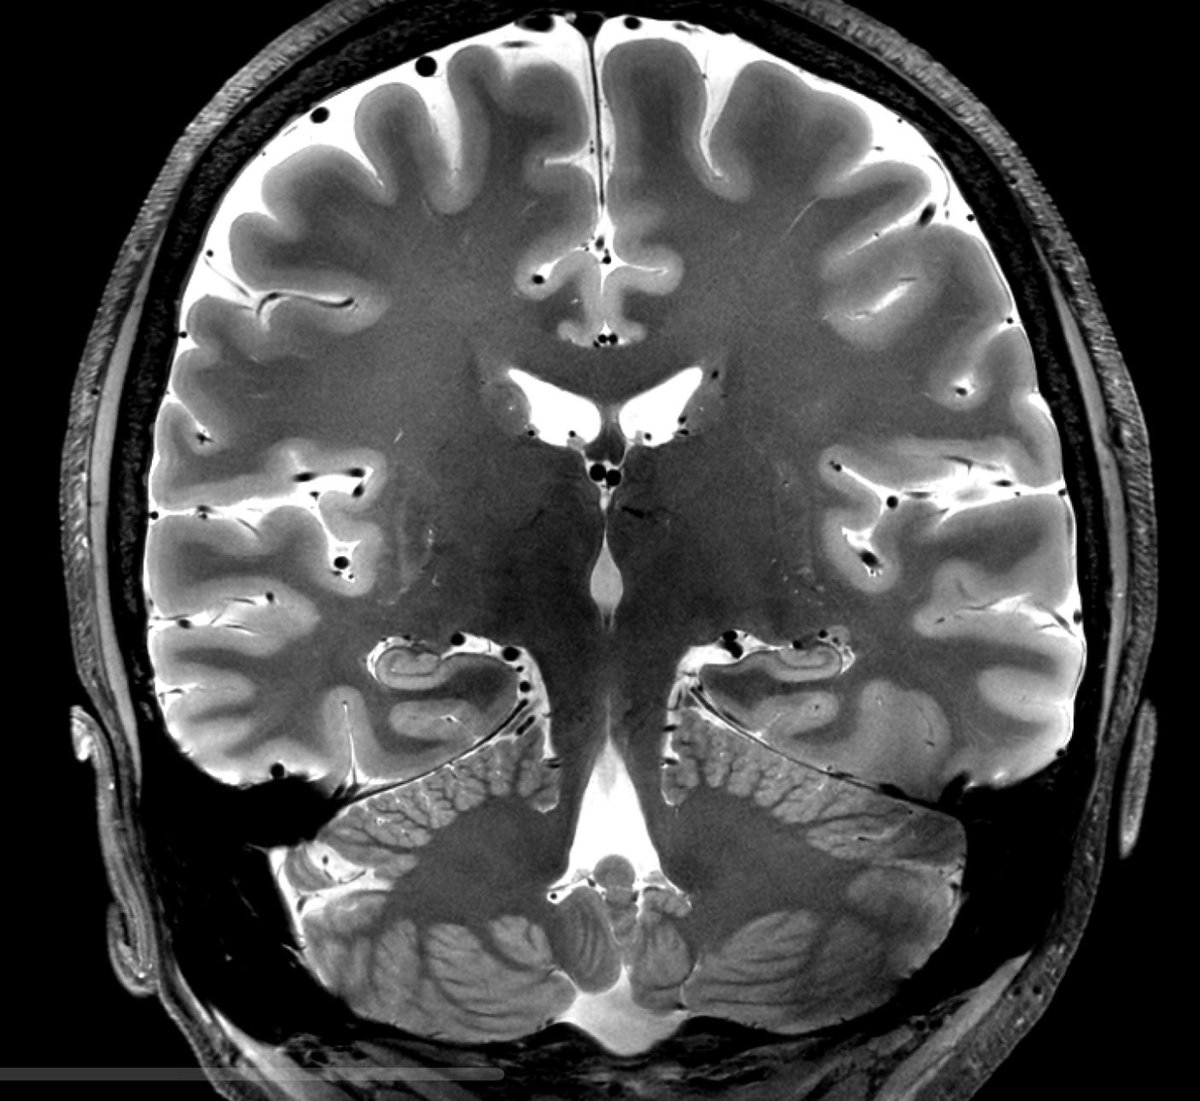

Milestone week for #7T program at #MayoClinicFlorida — we’ve scanned over 4000 clinical patients, including >1000 #epilepsy evals, >900 #MS patients, & many more! We have come so far & helped so many, but only getting started! Many amazing things on the horizon! @MayoRadiology